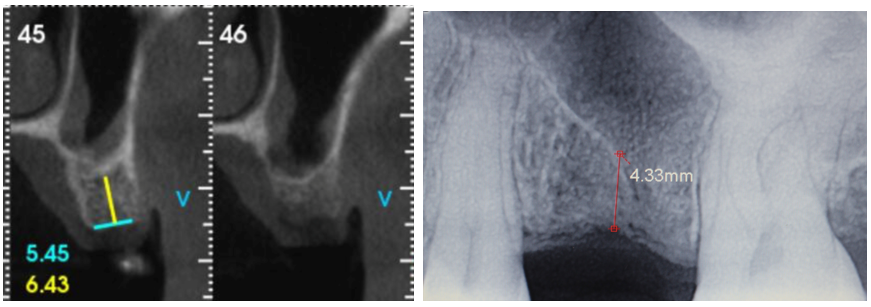

A paciente retornou após seis meses demonstrando clinicamente aspecto de mucosa queratinizada no rebordo alveolar (Figura 8) e, após abertura de retalho, vimos um rebordo ósseo saudável, com ligeira perda de espessura vestibular (Figura 9). A imagem tomográfica e a radiografia periapical sugerem formação de mais de 4 mm de altura óssea, além de ausência de sinusopatia (Figura 10), o que favorece a utilização do CAS Kit Osstem. Foi feita a fresagem cuidadosa com fresas CAS, promovendo o rompimento da cortical do seio maxilar, sem qualquer injúria à mucosa sinusal (Figura 11). Com o sistema de pressão hidráulica de injeção de soro fisiológico (Figura 12), foi realizada a elevação da mucosa e, em seguida, este espaço produzido foi preenchido com enxerto ósseo bovino (Figura 13).